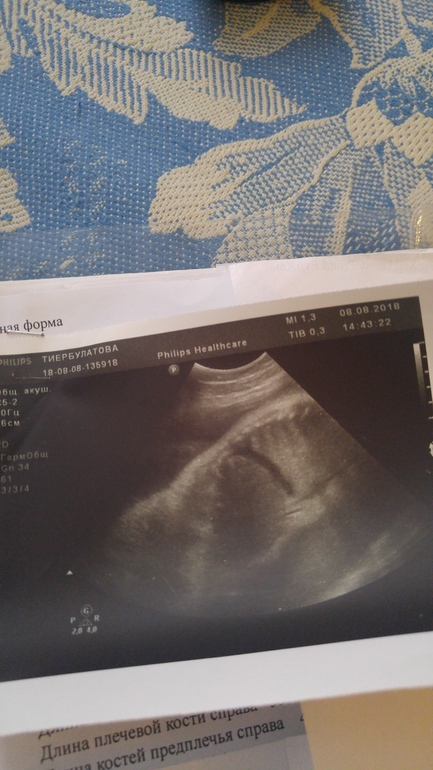

Прикладываю фото протокола узи и фото узи с этой жидкостью.

На узи нашли свободную жидкость в брюшной полости толщиной 6,5. Вот это меня пугает. Узист сказала,что надо в другом месте проверить, где аппараты получше. Сегодня на приеме была,делали ктг. Прием как в тумане, из-за переживаний даже не сообразила спросить, что делать и из-за чего это может быть. Гинеколог записала в перенатальный центр,но на 23.08.